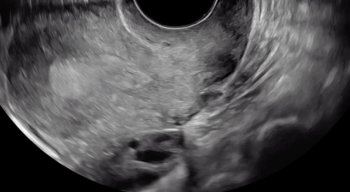

Pressure is being applied to the uterus by the ultrasound operator’s non-scanning hand, eliciting smooth sliding of the posterior uterine serosa over the bowel. Some fluid is noted within the rectouterine pouch, which often suggests a non-obliterated pouch

A hypoechoic deep endometriosis nodule is noted within the hyperechoic uterosacral ligament, infiltrating the parametrium